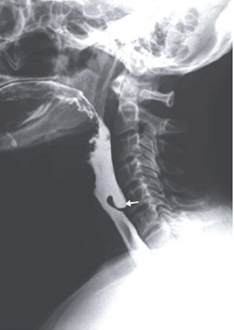

Paciente de 58 anos com queixa de dor cervical, engasgos ao se alimentar e regurgitação de alimentos não digeridos. Realizou exame de radiografia contrastada ao lado:

O tratamento deve ser indicado em pacientes sintomáticos ou assintomáticos com bolsa (tamanho do divertículo ao exame contrastado) maior que 3 cm.